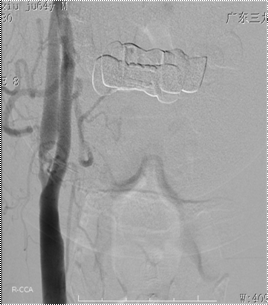

颅脑MRI提示:双侧基底节、放射冠区多发腔隙性脑梗死(如图一);颈部血管彩超提示:双侧颈动脉重度狭窄。3D-ASL提示:右侧额叶局部灌注减低,感兴趣区CBF测值为(28.39±12.97)mL/100g/min,低于对侧镜像感兴趣区测值(57.15±13.80)mL/100g/min(如图二)。DSA示:1、双侧颈内动脉起始部重度狭窄,狭窄程度均约90%,右侧狭窄长度约8mm(如图三);2、左侧颈总动脉末端中度狭窄,狭窄程度约50%,狭窄长度约1.0cm(如图四)。

图三